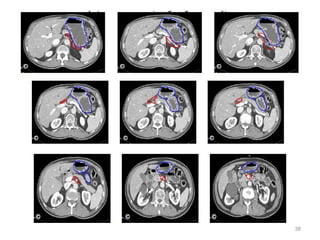

CONTOURING OF TARGET VOLUMES AND

ORGANS AT RISK

24

• Target volume for all gastric cancers would include body of pancreas, full

stomach bed and all regional nodes. Depending on part of stomach

involved, CTV may include also diaphragm, duodenum or lower

esophagus.

• Definition of Target

Volumes

Anastomoses

Gastric bed

Lymph nodes

•Definition of OARs

Kidneys, liver,

lungs, heart, sp

cord

Target and OARs